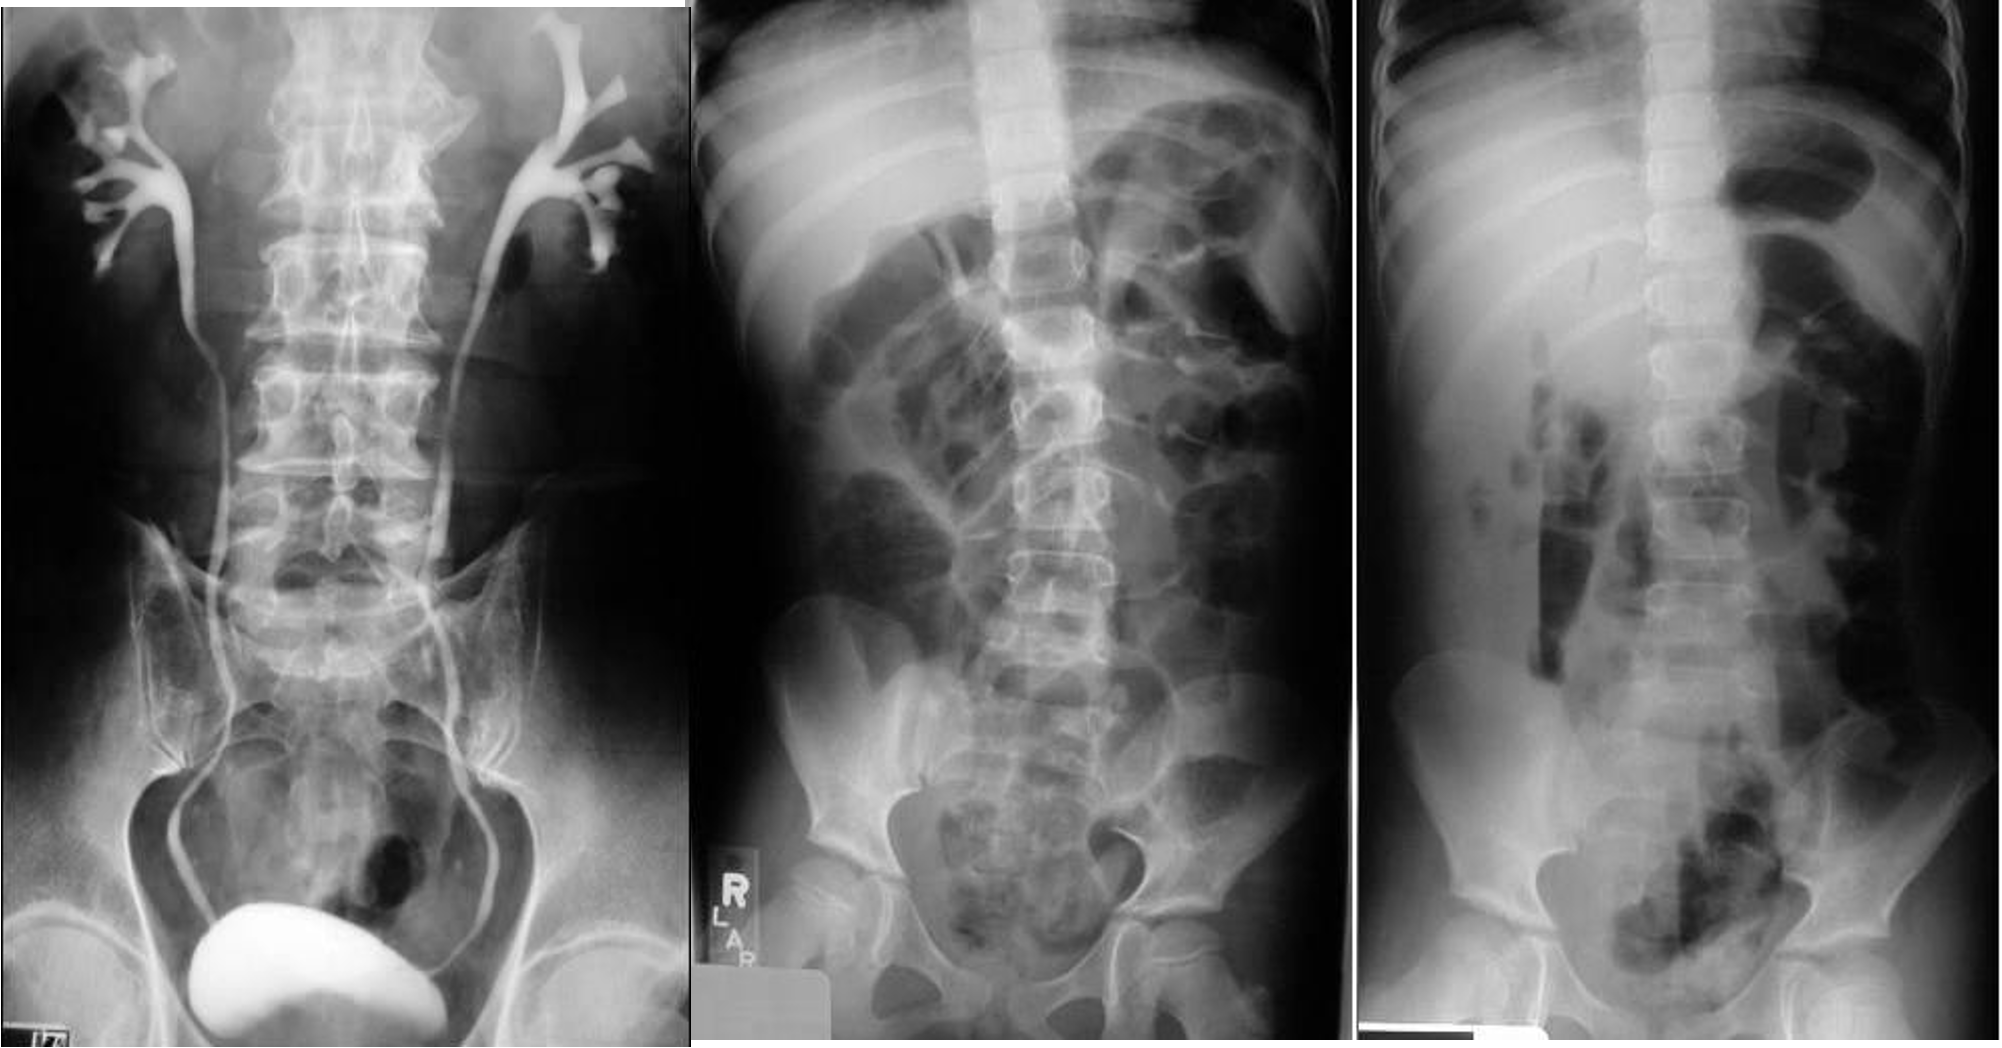

Pyelo

- & 2 Appendicitis - appendicolith/feacolith in young, MALT GALT

- IVP, normal

- IVP, Hydrouterer - sharp blunted

- Uretic stone

- radioopaque shadow on RUQ - renal stone